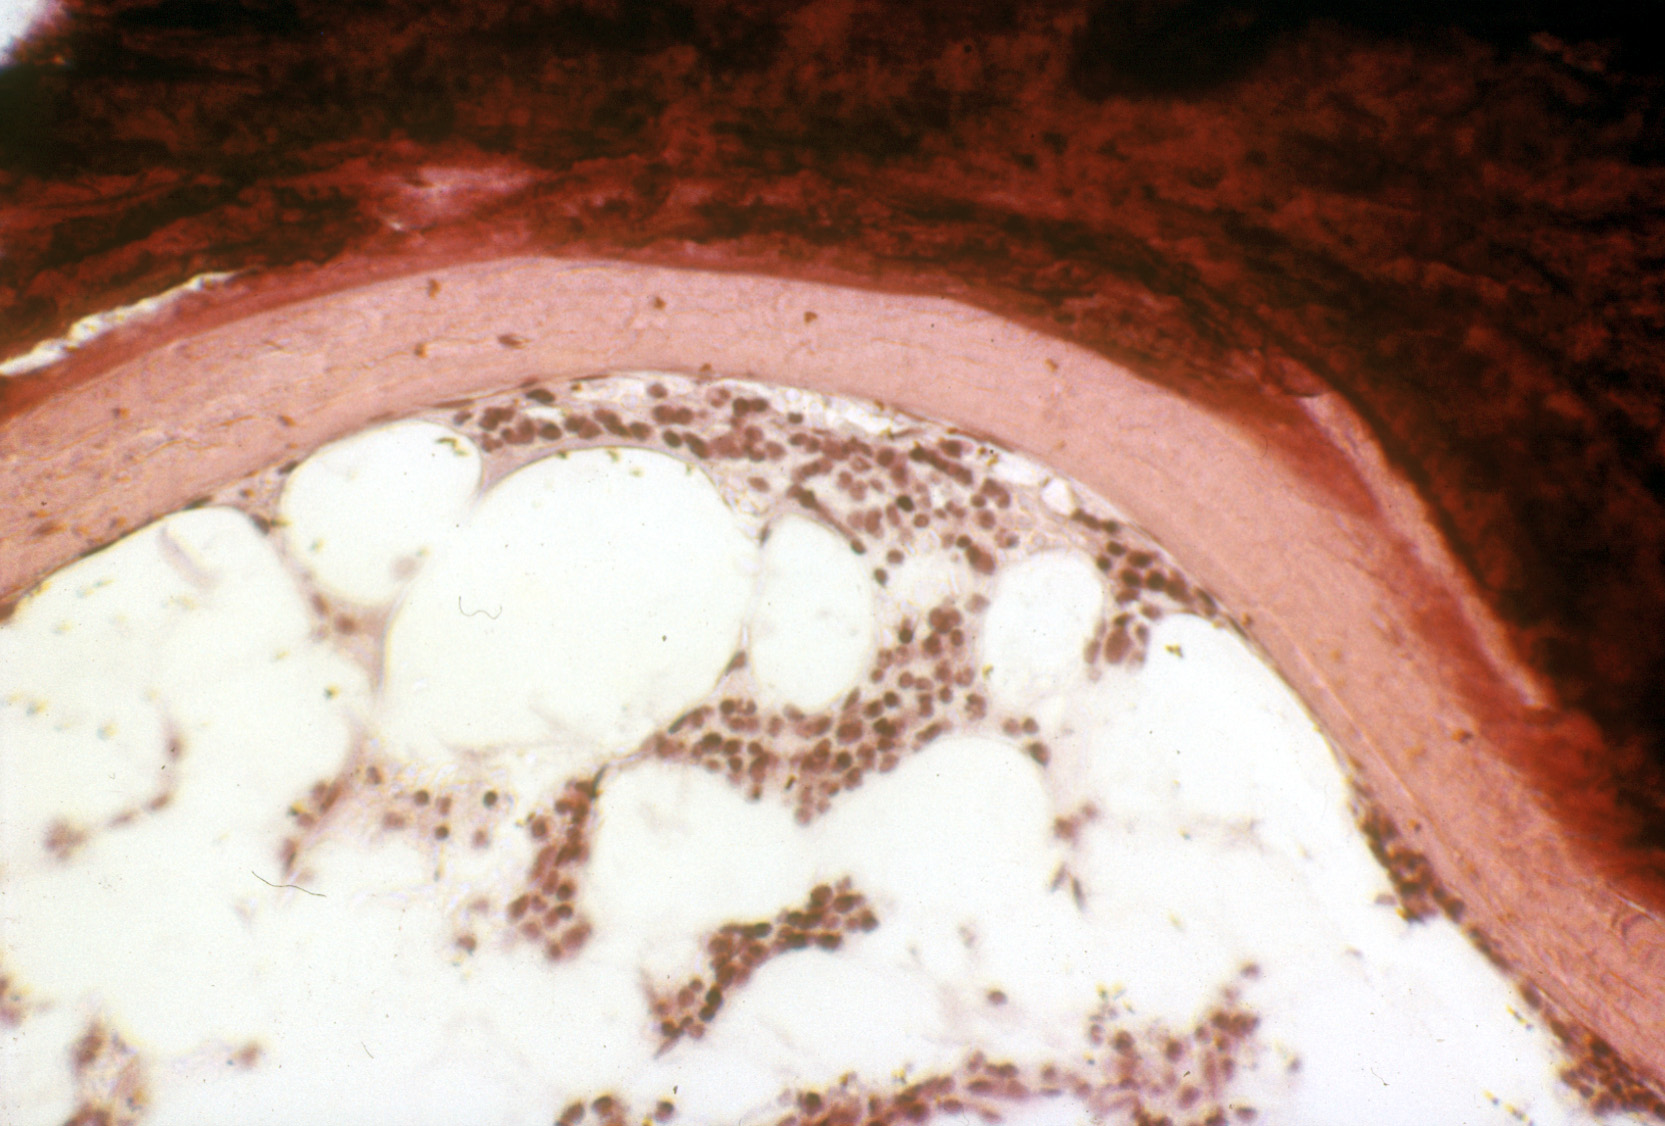

Рис. Остеомаляция. Видна широкая зона остеоида. Недекальцинированный срез. Окраска по Коссу. х400."

Остеомаляция, как и рахит, характеризуется наличием патологического остеоида, формирующегося в результате отсутствия или замедления обызвествления новообразованных костных структур в процессе перестройки кости.